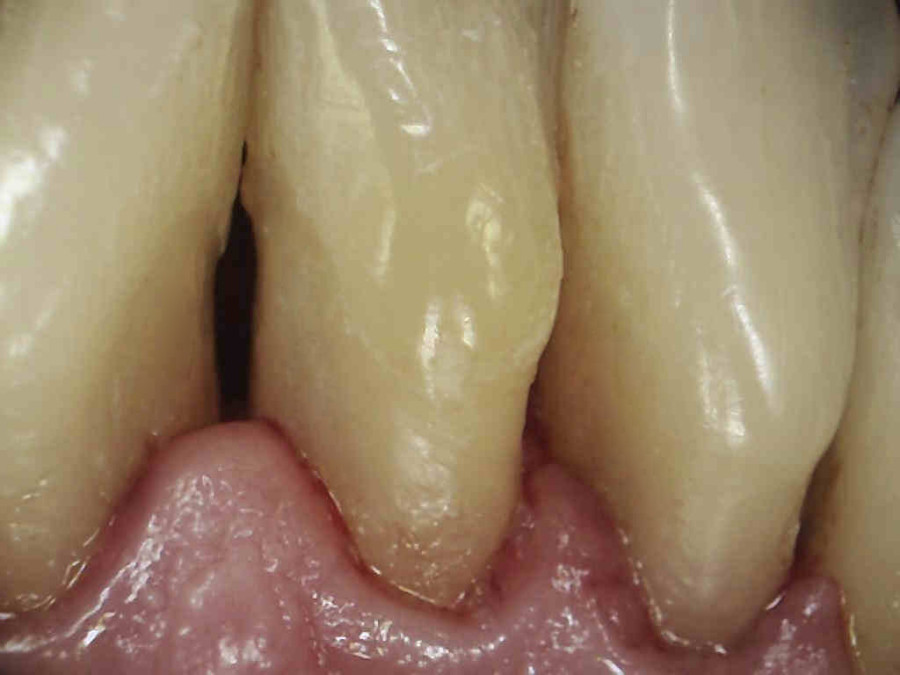

Naszym celem jednak jest nie tylko ładny wygląd zębów ale wyleczenie stanu zapalnego dziąseł, a to nie będzie możliwe bez dokładnego wyedukowania pacjenta. Higienistka przeprowadziła szczegółowy instruktarz prawidłowej metody szczotkowania – pokaz na modelu i samodzielna próba pacjenta na własnych zębach. Pacjent nauczył się również stosowania szczoteczek międzyzębowych, będących w jego przypadku niezbędnym akcesorium higienicznym ze wglądu na szerokie przestrzenie miedzyzębowe. Zalecone zostały środki pomocnicze – Eludril do płukania, pasta Elgydium Anti-Pacjent spotkał się z nasza higienistka jeszcze dwa razy, w celu dokonania kontroli i ewentualnego doczyszczenia. Na drugiej wizycie kontrolnej dziąsła pacjenta wyglądały tak: zdjęcie 3, zdjęcie 6. Komentarz jest chyba zbędny: różnica widoczna gołym okiem, dziąsła są zdrowe, bladoróżowe, bez opuchlizny. Gratulujemy!!!